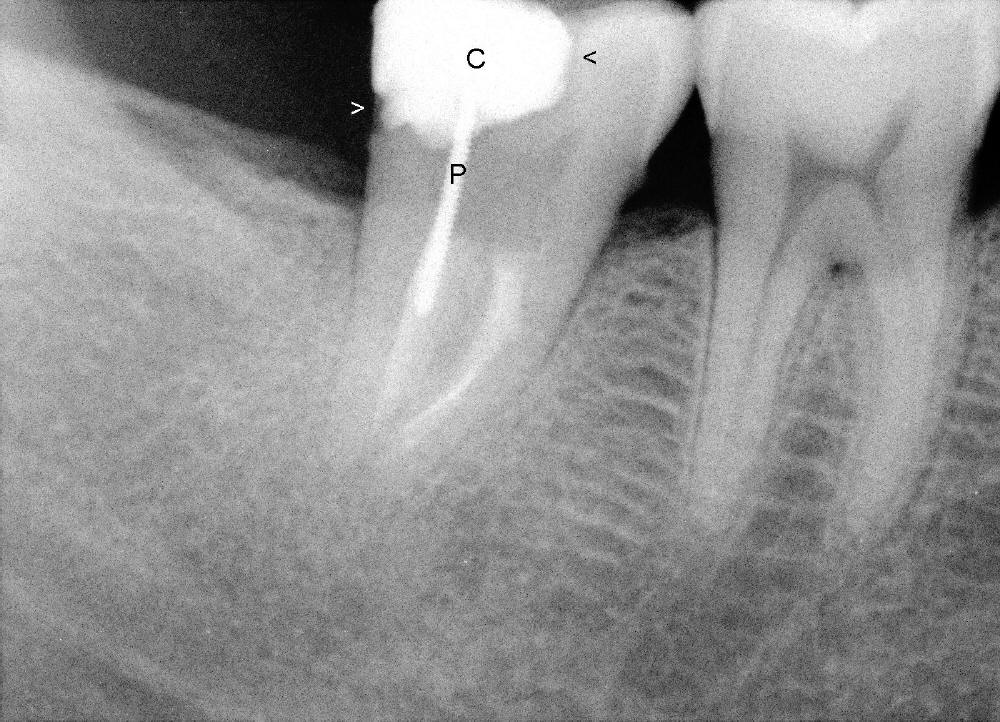

A 50-year-old lady presents to clinic with chief complaint "I need a new filling in the lower right".  Root canal has been done in her home country without symptoms for several years.  Exam reveals that the tooth #31 has DO composite.  The mesial portion of the restoration has chipped (Fig: black arrowhead).  There is 2nd caries in the distal margin (white arrowhead).  Percussion reveals minimal tenderness.  Crown is recommended.  In addition to the post (P) and core (C), what is special about this case?